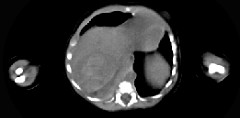

- 单项选择题男,刚刚出生5天, 上腹部膨隆,CT所见如图, 最可能的诊断为 ( )